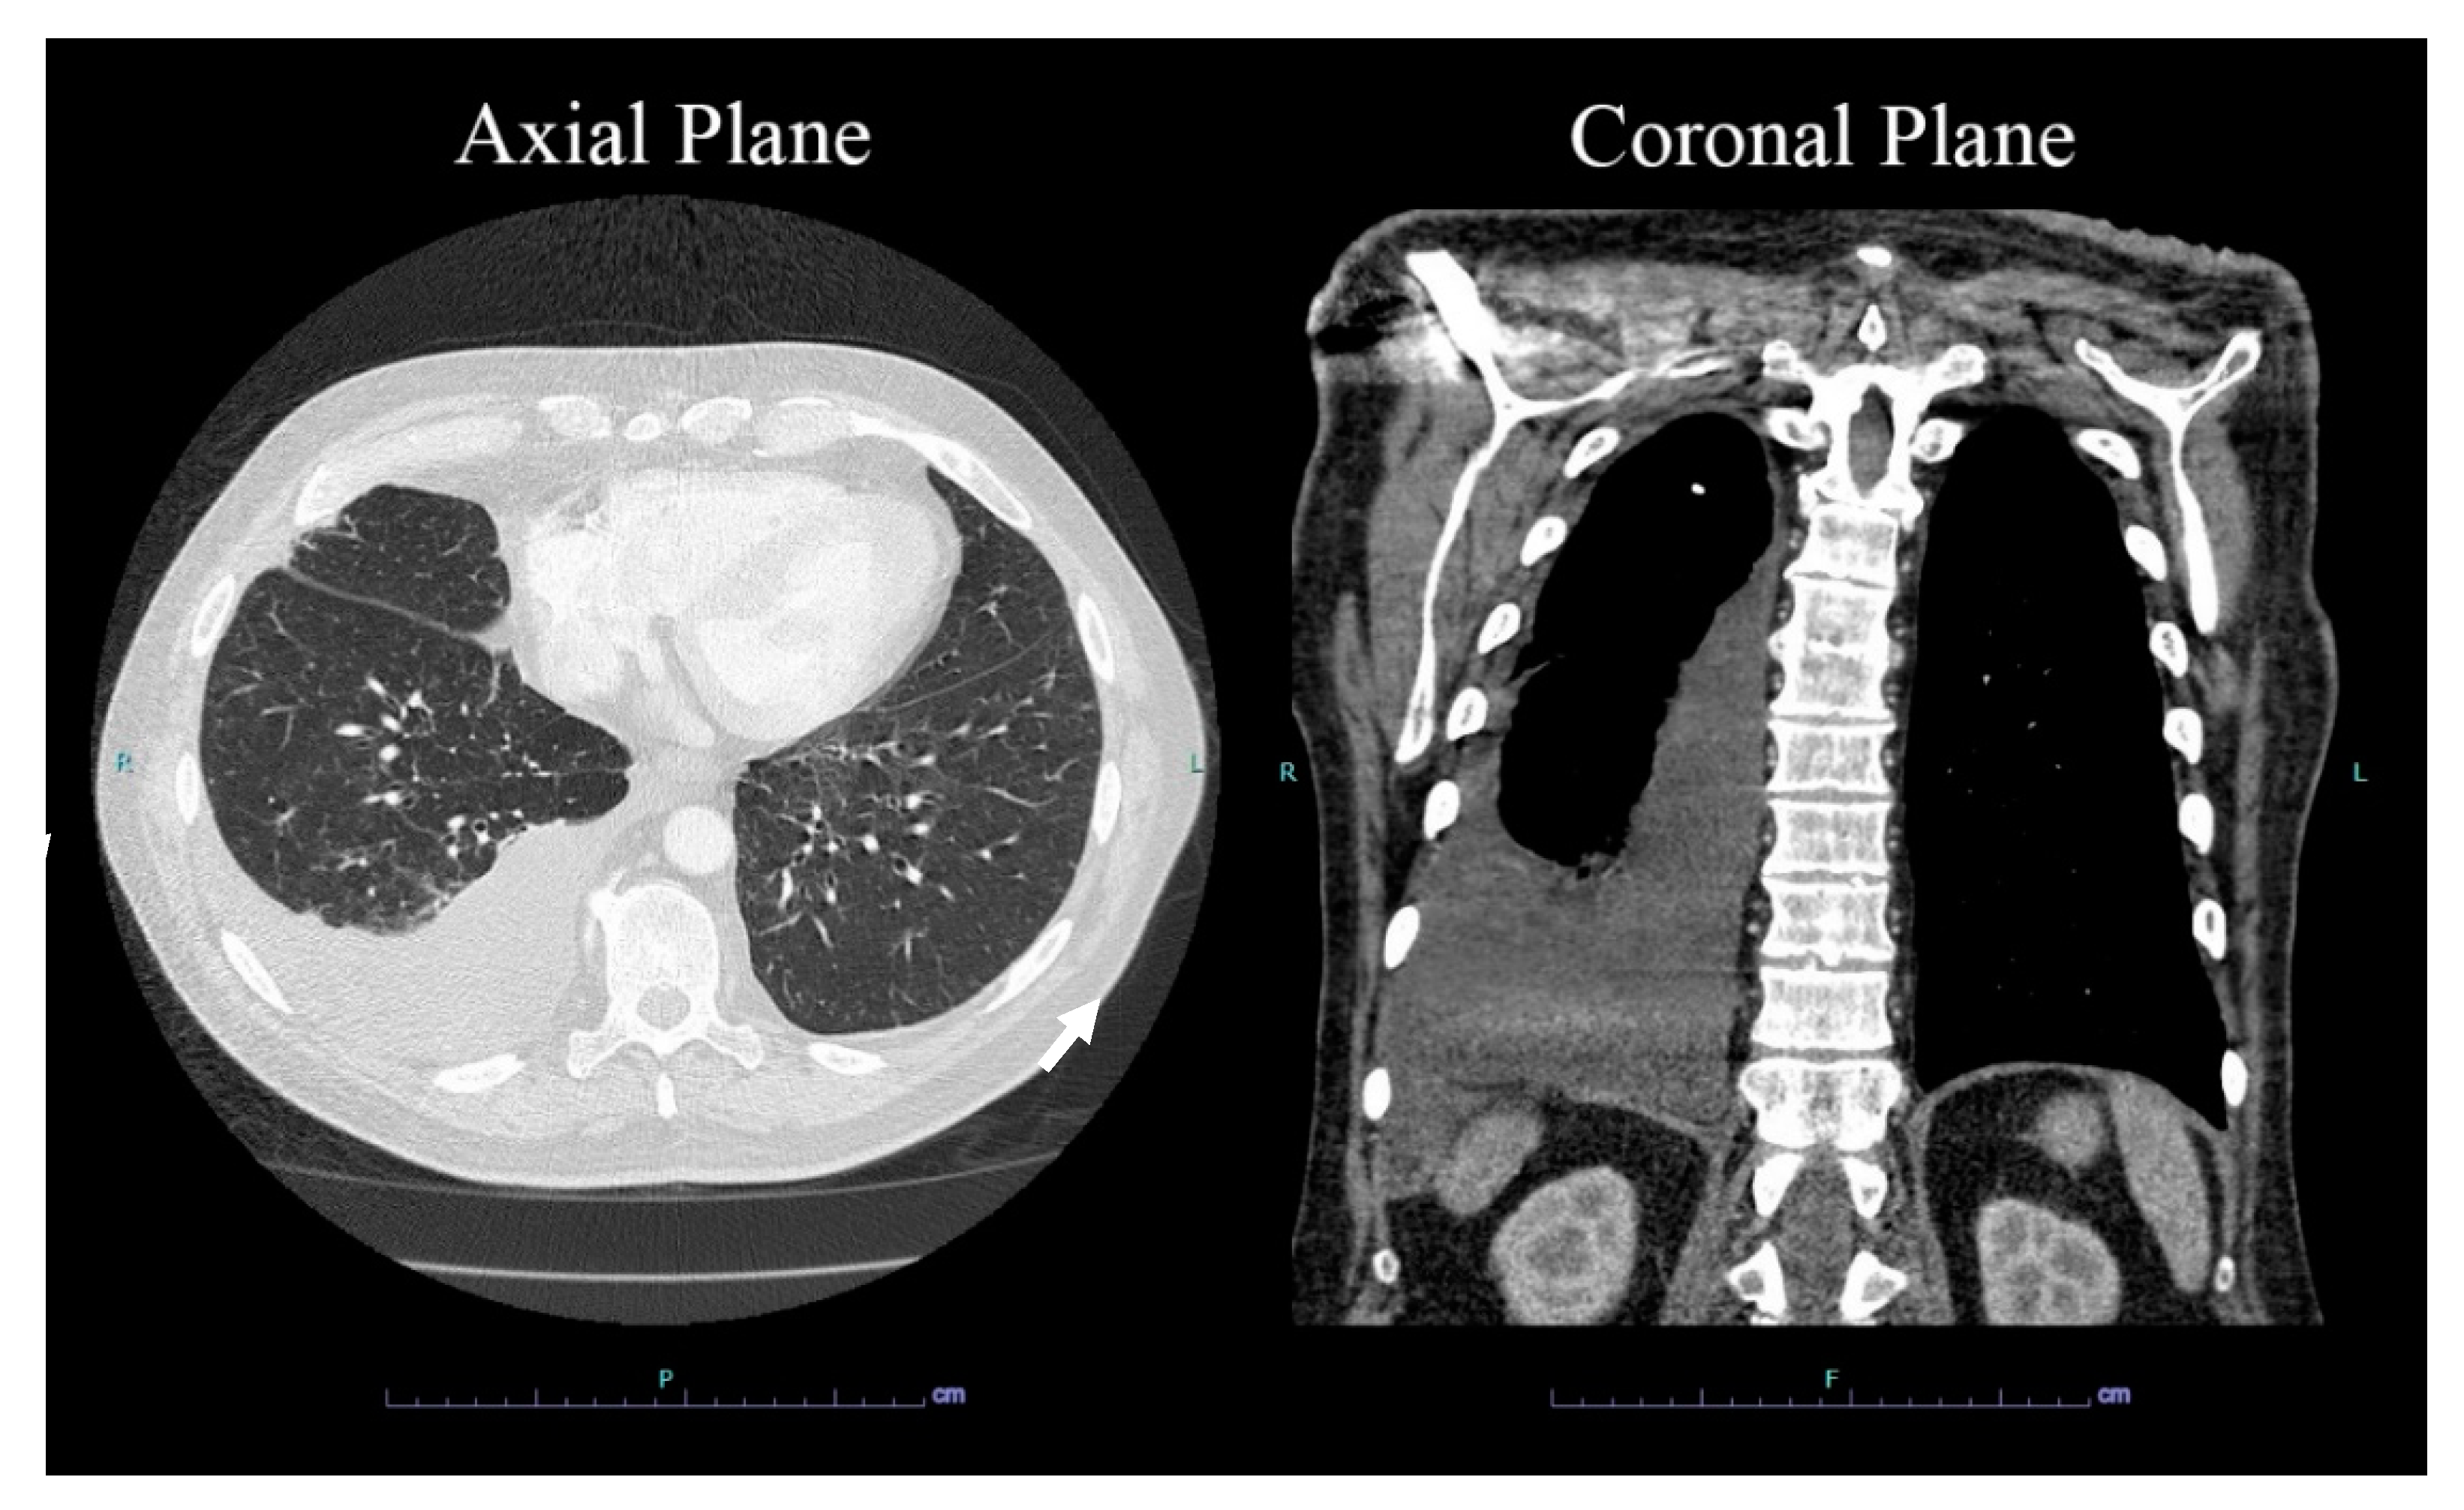

2. Case Presentation